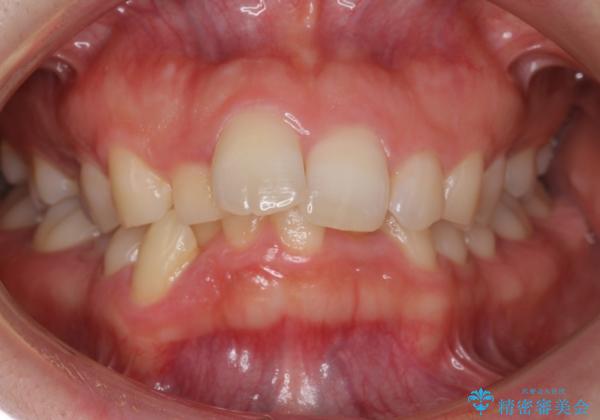

- 前歯のがたがたと出っ歯を主訴に来院。

CTを撮影したところ、臼歯部の頬側の骨の厚みが非常に大きく、通常では考えられない量の歯列の拡大が可能でした。

今回は健康を損なわずに非抜歯で治療が可能でしたが、

歯ぐきや骨の厚みが薄い他の患者さんでは難しいです。

左上5は180度捻転していましたので、そのまま並べています。

遠心移動などは行わず、IPRと拡大のみで治療を行いました。

一般的に非抜歯矯正を無理に行うと、口元がモッコリ出てしまうことがあります。しかし、今回は前歯を前に出さないような設定にしており、口元が出ることもありませんでした。